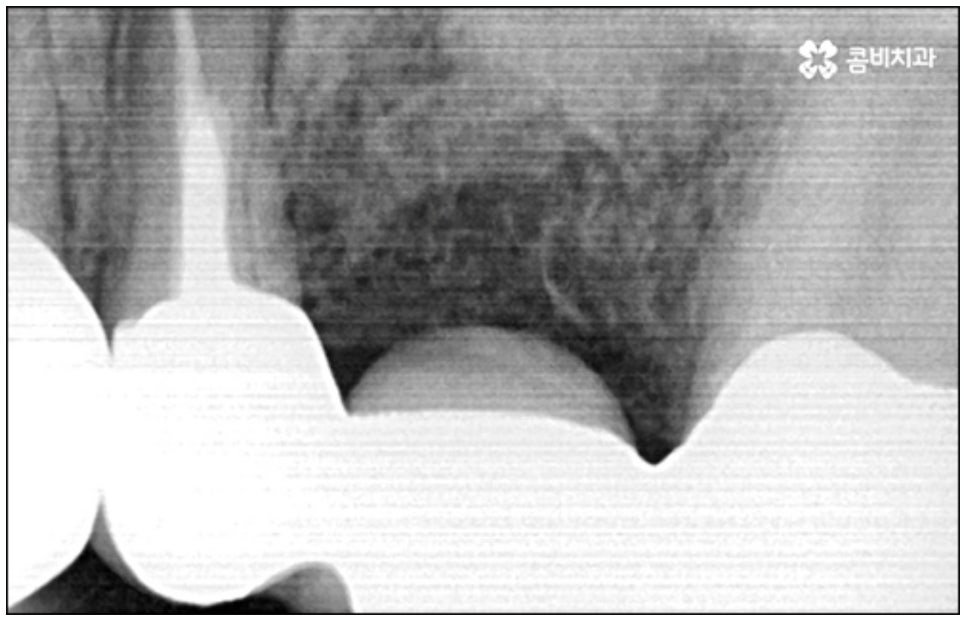

치아를 상실한 채 오랫동안 방치하게 되면 위에서 언급한 기능적 심미적인 문제 외에도 치조골이 점차 흡수되는 골소실이 일어나 주변 다른 정상적인 치아에도 영향을 끼치게 되며 이를 통해 치열이 틀어지게 되거나 턱관절 통증 및 장애 등이 유발될 수 있으니 늦지 않게 치과에 방문하셔서 검진 및 치료를 받으시길 바라고 있어요.

예를 들어서 오랜 치주염으로 퇴축이 진행되어 잇몸이 이미 많이 내려앉은 경우, 심한 치아 뿌리 염증으로 잇몸뼈가 상당부분 녹은 경우, 노화나 지병으로 인해 골밀도가 낮고 잇몸뼈가 약해져 지지가 어렵거나 쉽게 부서지는 등 뼈의 상태가 양호하지 못한 경우 등에 있어서는 발치 후 즉시 임플란트를 식립하는 방식이 적합하지 않으며 치아가 한꺼번에 여러개 손상된 경우에도 6~8주 정도의 시간을 두고 무리하지 않게 단계적으로 식립하는 것이 혹시 모를 부작용을 막고 장기적인 안정성을 높이는 방법이라고 할 수 있어요.

이때 당일임플란트 시술은 정밀함을 요하는 고난도 치료에 속하는 만큼 의료진의 숙련도에 영향을 많이 받기 때문에 안정적으로 골이식재가 자리잡고 식립된 임플란트가 보다 오랜 기간 강한 저작력을 견딜 수 있도록 지속력을 높이기 위해서는 다양한 환자분들의 임상 치료 경험과 뛰어난 노하우, 정확한 판단력 및 세심한 실력을 갖춘 의료진에게 시술을 받으실 필요가 있습니다.